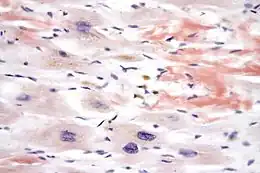

Coupe histologique d'une amylose cardiaque, à l'origine d'une cardiomyopathie restrictive. Coloration au rouge congo.

Elle peut être idiopathique (aucune cause n'est identifiée), ou secondaire à diverses pathologies telles qu'une fibrose endomyocardique (tropicale, syndrome hyperéosinophilique idiopathique), une maladie infiltrative (amylose, sarcoïdose), une maladie métabolique (maladie de Gaucher, mucopolysaccharidoses, maladie de Fabry, syndrome carcinoïde). Elle a également été décrite dans les suites de radiothérapie ou de certains traitements médicamenteux (dont la chloroquine[2]).